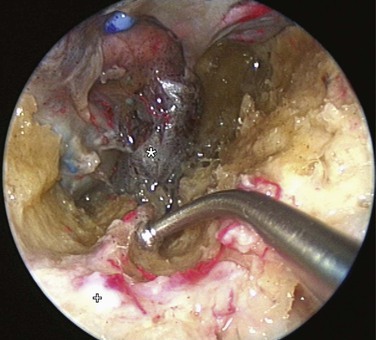

If bleeding cannot be controlled after endoscopic examination and cautery and/or nasal packing, sedation and examination under a local or general anesthetic are indicated. Bipolar diathermy of any bleeding points or ESPAL is then the treatment of choice.10 Clipping or diathermy of the sphenopalatine artery is currently the accepted treatment for management of persistent posterior epistaxis,50,62,68-72 because it produces less morbidity compared with embolization or ligation of the maxillary or external carotid artery.73,74 The main complication in 25% of patients was nasal crusting. Pooled case series data have shown that 98% of patients had epistaxis controlled by clipping or diathermy of the sphenopalatine artery.75 The endoscopic sinus surgeon should locate the sphenopalatine artery at the level of the ethmoid crest (Fig. 42-17).75 An incision is made over the posterior fontanelle, a submucosal flap is lifted, and the anterior branch is identified with its origin just posterior to the crista ethmoidalis. The anterior branch is then identified and is either clipped or diathermied (Fig. 42-18). In the majority of cases, the sphenopalatine foramen opens into the middle and superior meatus.